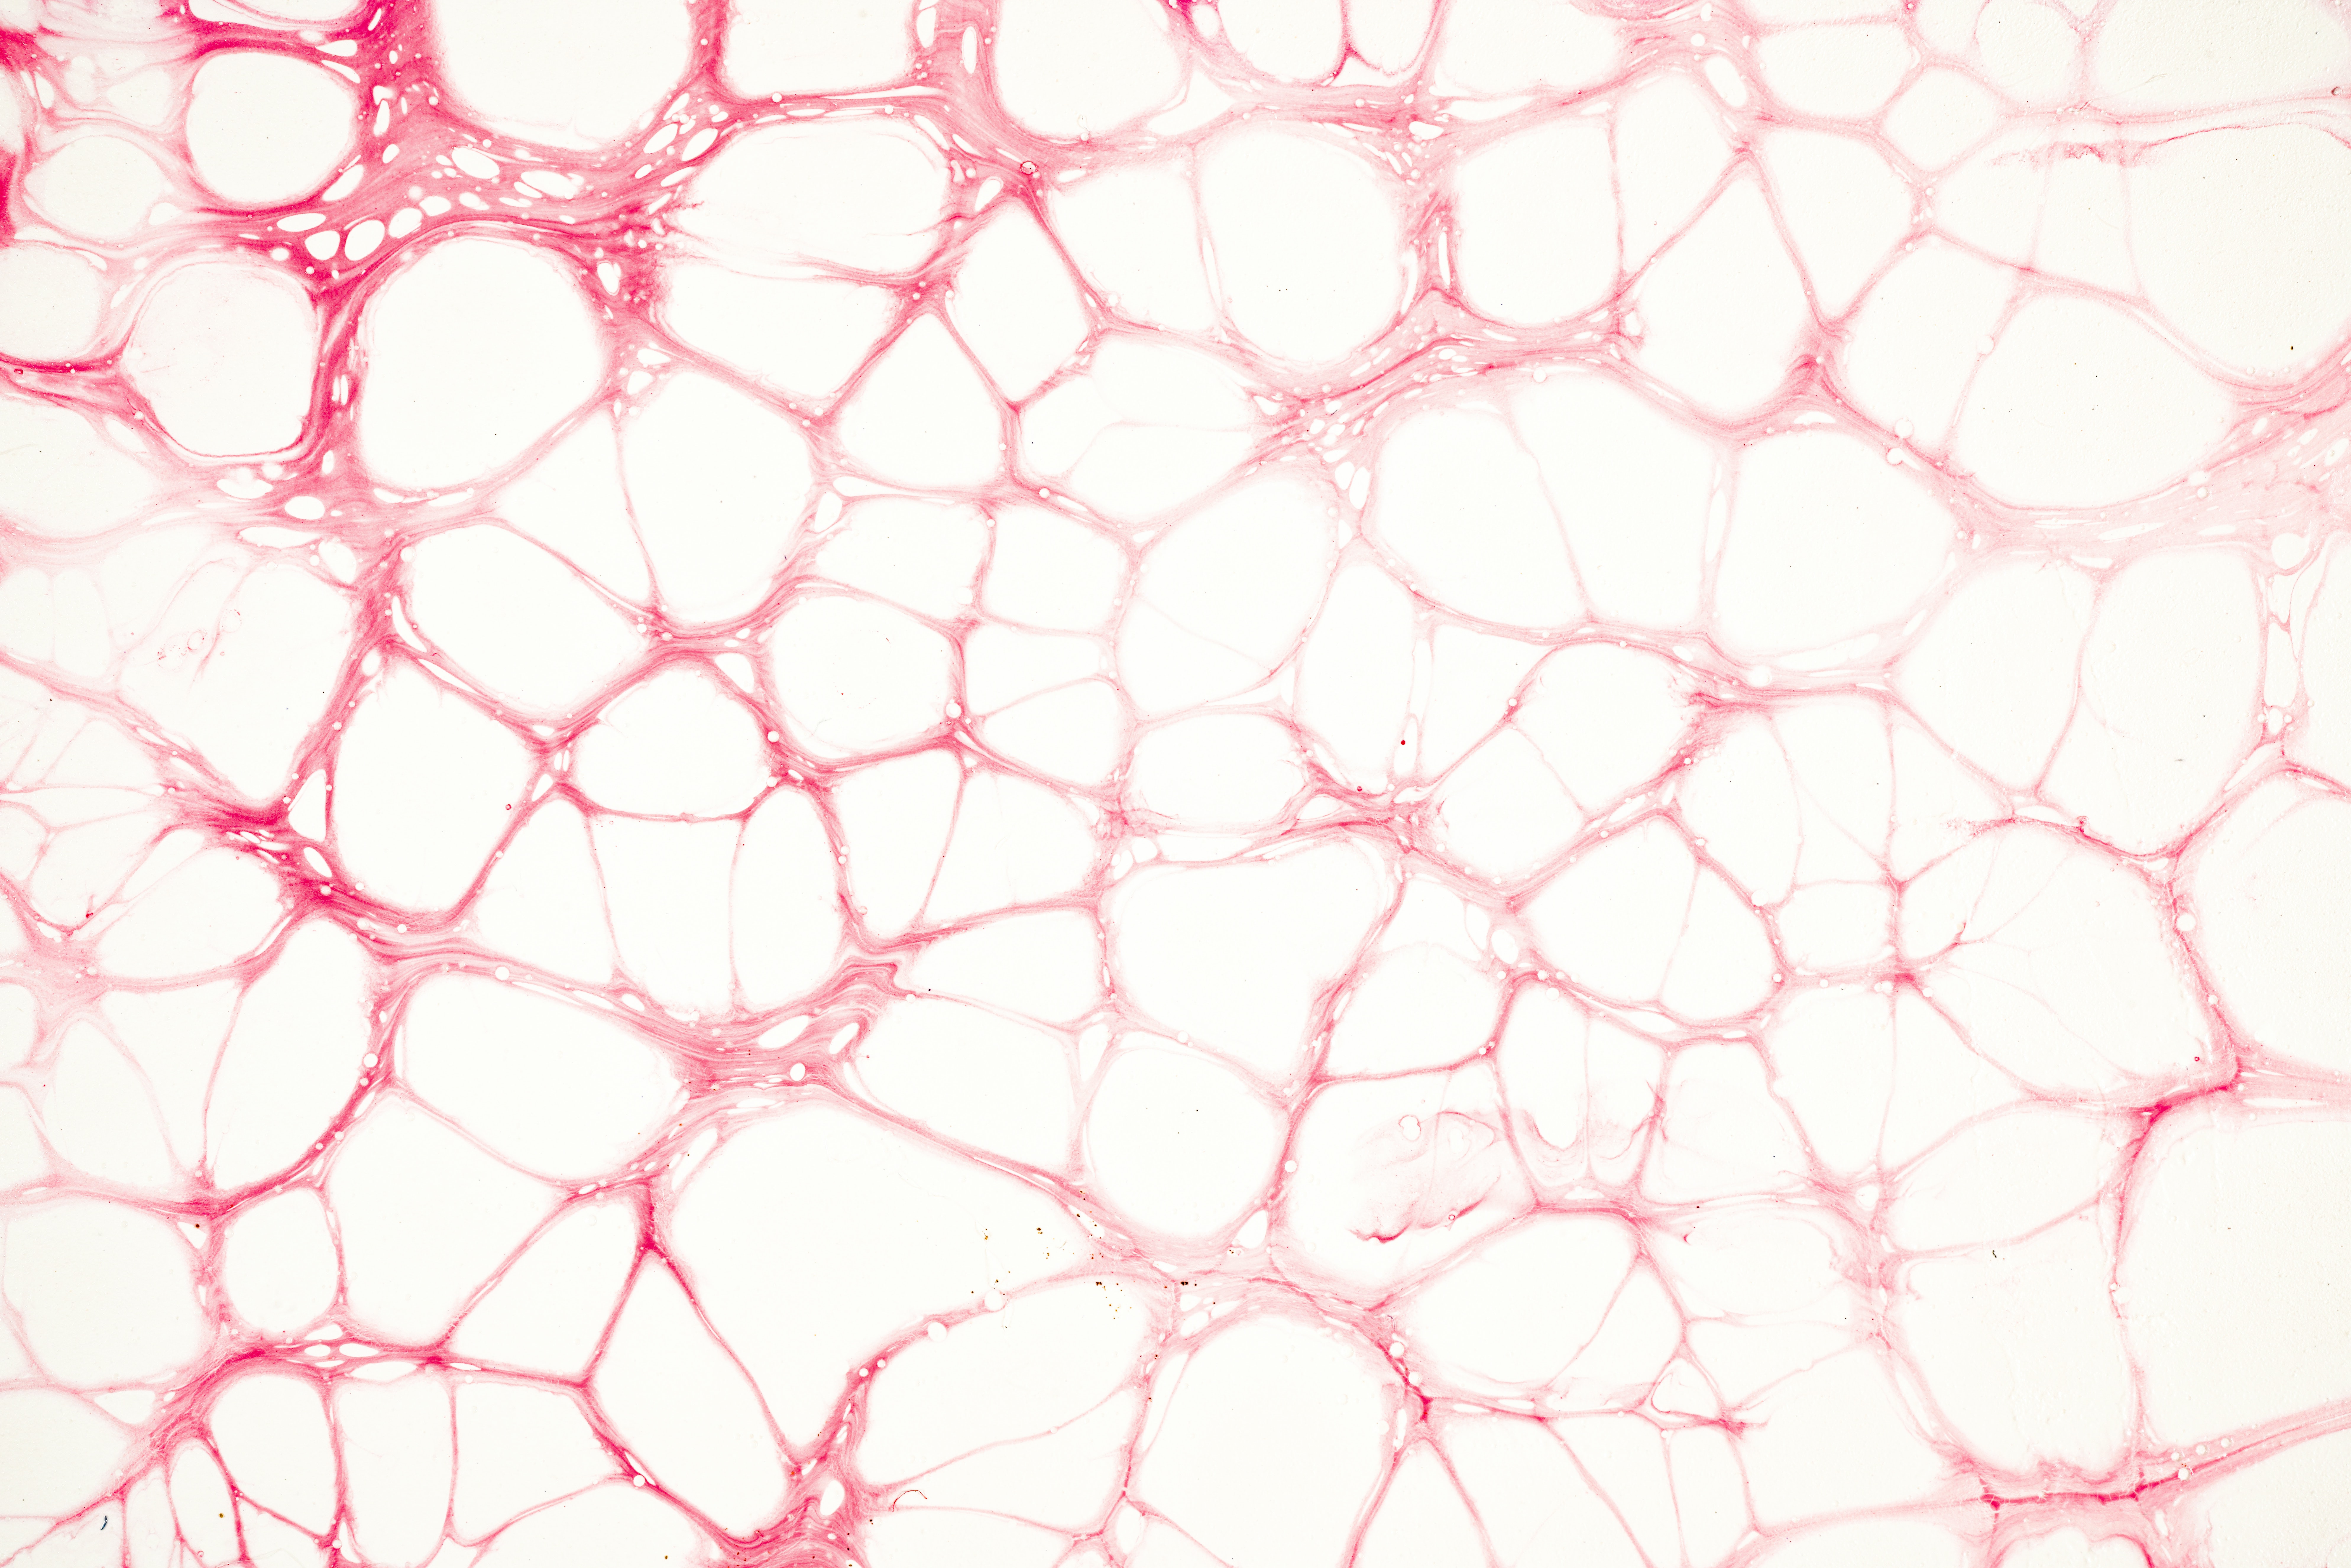

Los TNE comprenden un gran grupo de tumores muy variables que se originan a partir de células neuroendocrinas. Estos pueden aparecer en prácticamente cualquier órgano del cuerpo, aunque las localizaciones más frecuentes son el tubo digestivo, el páncreas y el pulmón.